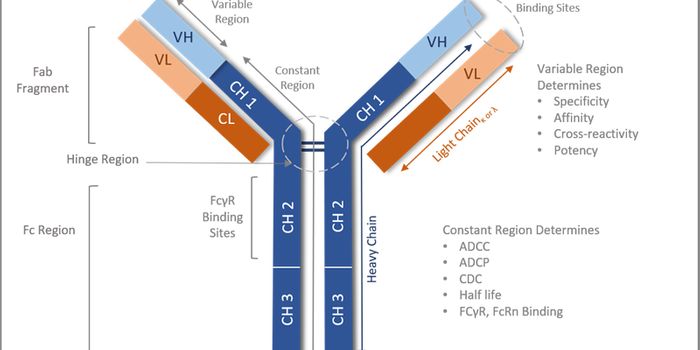

APR 11, 2023CancerMonoclonal antibodies have revolutionized cancer therapy since their introduction as therapeutics in the field. To enhan ...

MAR 21, 2023Drug Discovery & DevelopmentTherapeutic antibodies are one of the best-selling drug classes in the pharmaceutical market, and the advent of antibody ...

JUL 18, 2023Drug Discovery & DevelopmentEvolution of Antibody Humanization and Affinity Maturation Antibodies play a vital role in the immune system by providin ...